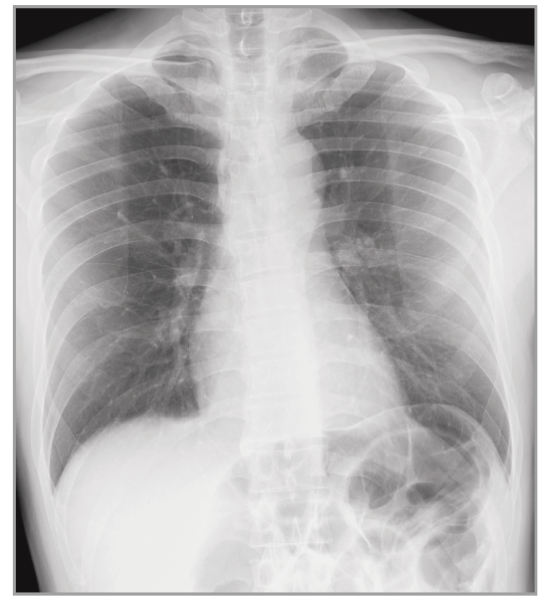

Virtual Grid

Provides a high quality image without using a grid

Virtual Grid processing corrects for the effects of scatter radiation. Without the need for a grid, Virtual Grid retains high contrast and image sharpness, while preventing the asymmetric density  resulting from misalignment of X-ray tube and detector. (Option)

Virtual Grid​

No Grid

Real Grid

Multiple body parts supported

Abdomen

Cervical Spine

Thoracic Spine

Lumber Spine